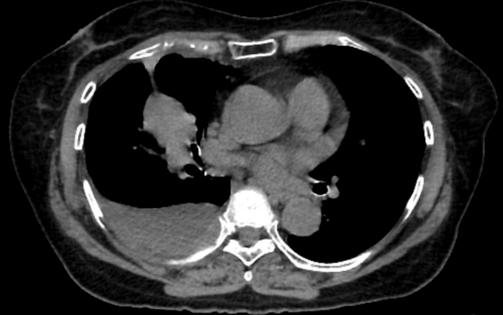

A single cross-sectional image from a chest CT shows a mass in the patient’s right lung and fluid surrounding the lung. RAJAAISYA/Science Photo Library via Getty Images